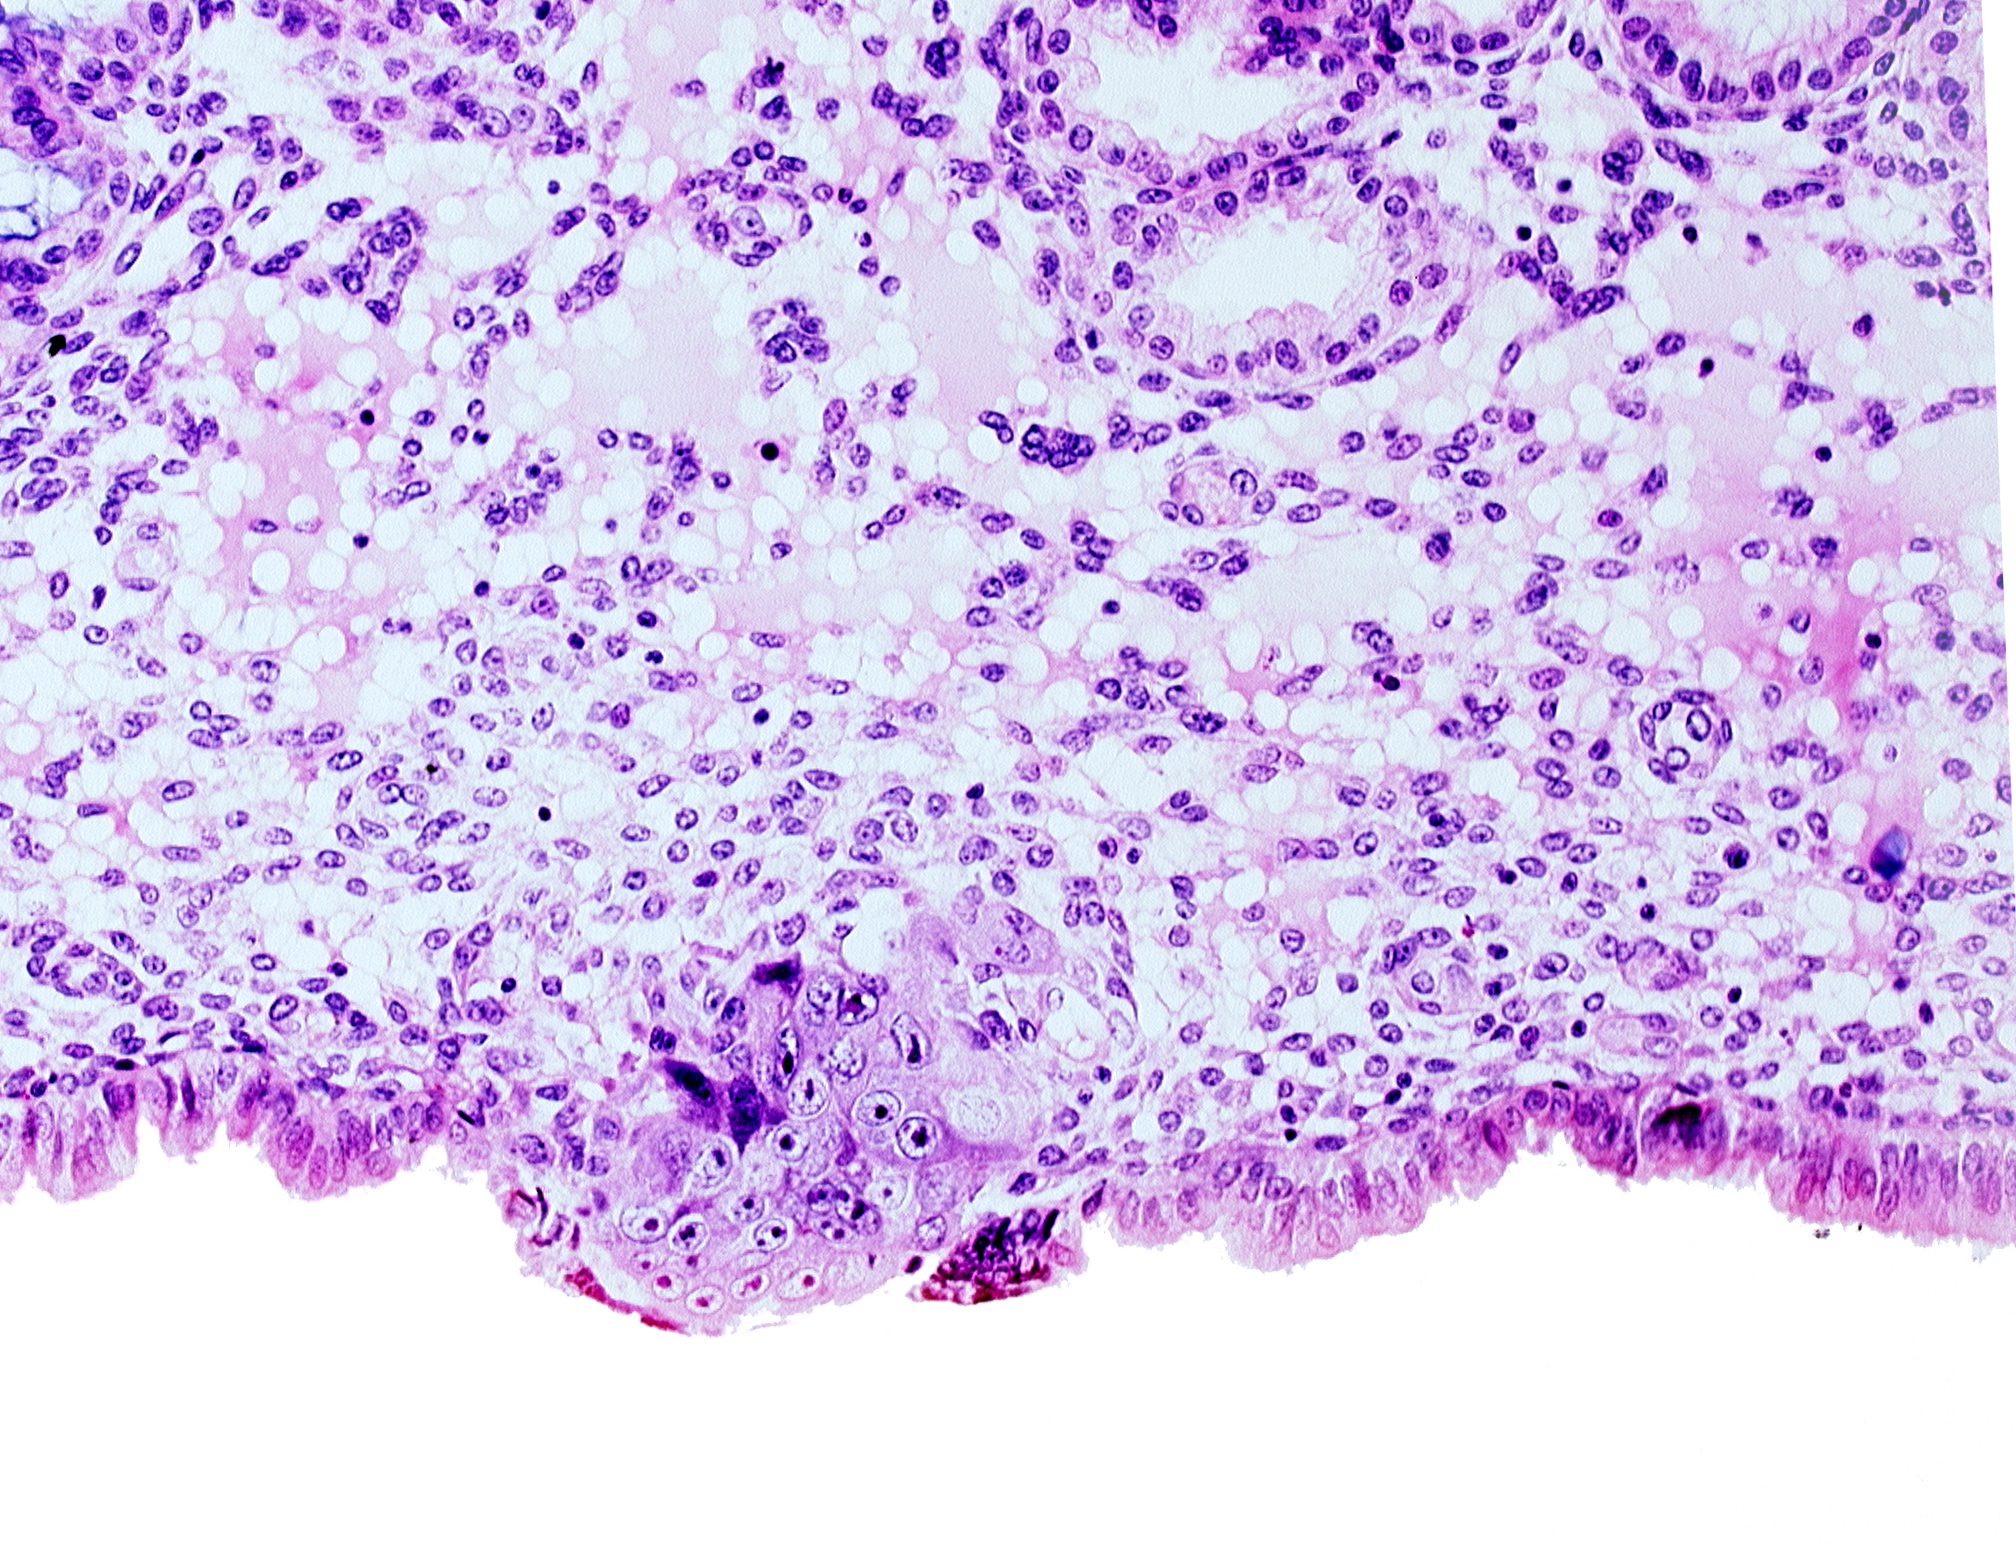

Carnegie Embryo #8155 | Location: 04-04-03

Keywords: cytotrophoblast, edematous endometrial stroma (decidua), endometrial epithelium, endometrial sinusoid, syncytiotrophoblast / decidua interface, uterine cavity

Source: The Virtual Human Embryo.